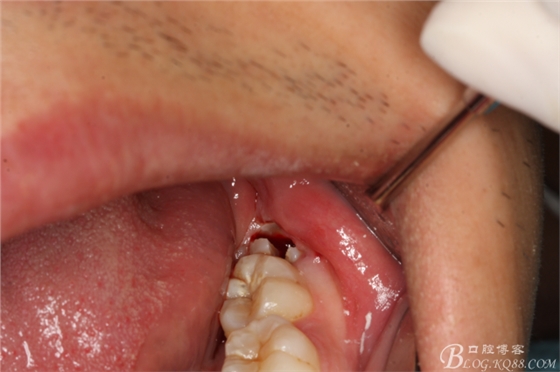

圖12.牙冠取出后,為牙根的脫位騰出空間

圖13,牙槽窩周圍牙齦幾乎無(wú)損